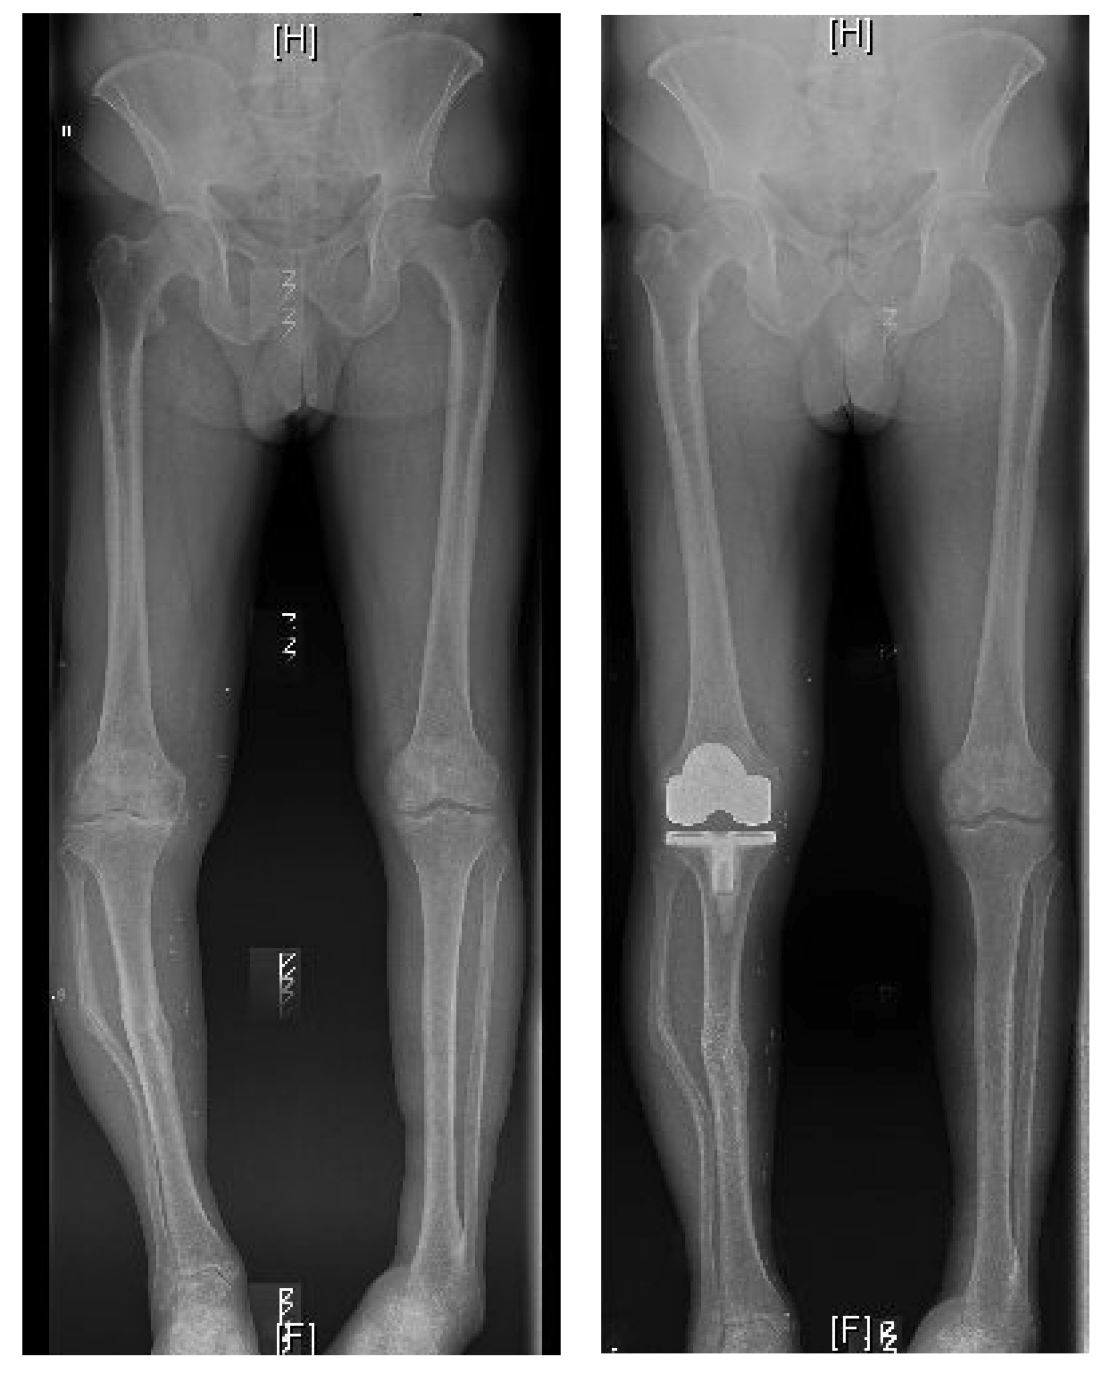

BILATERAL KNEE REPLACEMENT

"Enjoying Every Minute of It"

After many years of discomfort with both knees, endless amounts of injections, and getting nowhere I met Mr Vioreanu at the Sports Surgery Clinic in December 2014.

BILATERAL SIMULTANEOUS KNEE REPLACEMENTS

"Pain free and no limp at 3 months"

I am 40 years old and Mihai performed bilateral, simultaneous full knee replacement surgery for me just over three months ago. The surgery was a complete success. I now walk pain free and without any limp. I am living my life to the full again. I will be forever grateful for the outstanding level of care I received from Mihai and his clinical and admin teams.